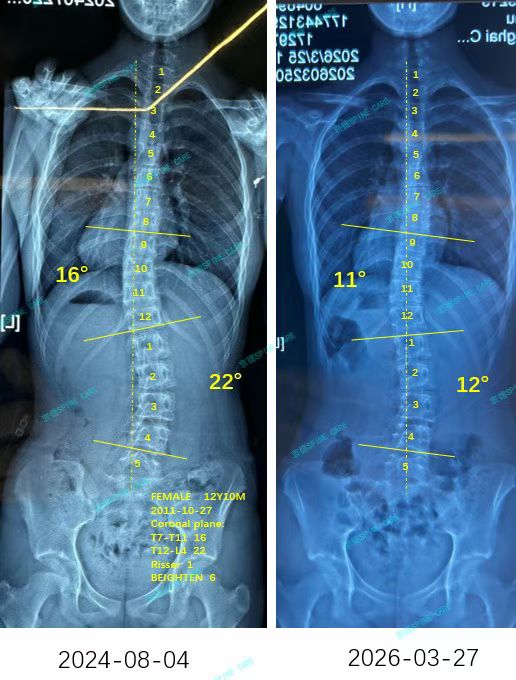

来自家长对衷德的评价(曦曦妈妈)

衷德脊柱,我们只关注侧弯保守治疗~

Zhongde Spine, bending no breaking ~